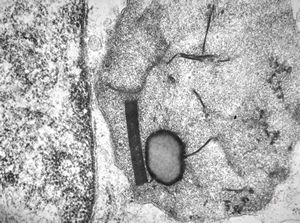

F,50y. | progressive multifocal leukoencephalopathy- viral particles in a glial cell